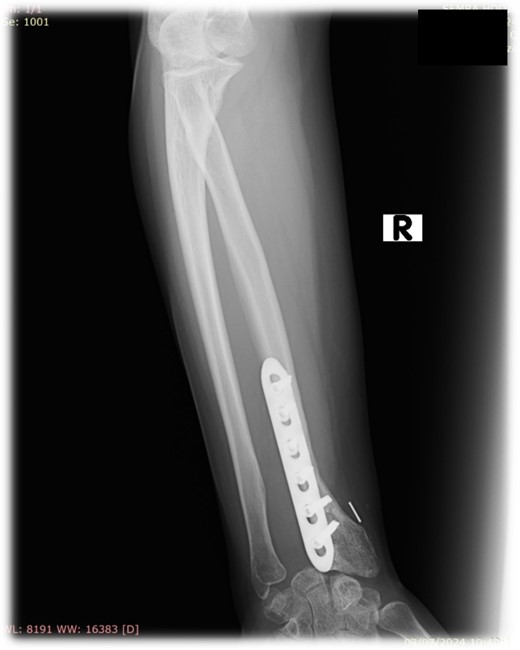

At 2 years follow-up, no clinical and X-ray signs of tumor recurrence or graft resorption were detected, both X-ray and CT confirmed that bone healing has been achieved (Figs 7 and 8) On physical examination, the patient has decreased wrist dorsal and palmar flexion, all other wrist movements are in normal range of motion and without pain (Fig. 9).

Follow-up X-ray of the right forearm 2 years after the surgery in profile plane

Follow-up X-ray of the right forearm 2 years after the surgery in anterior–posterior plane.